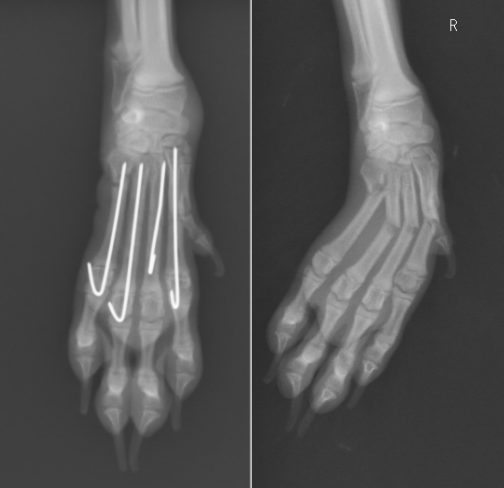

4本すべてが折れてしまった症例です。すべて0.6mmのピンが入っています。理想は関節に入らないことですが、3本は関節からの刺入以外は困難でした。